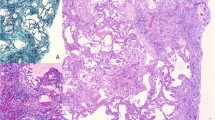

Lung samples from 38 subjects living in Barcelona and Ferrol, Spain, were studied, which were divided into three groups: Group A—five subjects without known respiratory disease; Group B—20 ex-shipyard workers and Group C—13 patients with lung cancer. After eliminating the organic material, the inorganic residue was analysed using electronic microscopy (EM). To identify the type of fibre, the samples were analysed by scanning electron microscopy (SEM) and energy-dispersive X-ray spectroscopy (EDX).